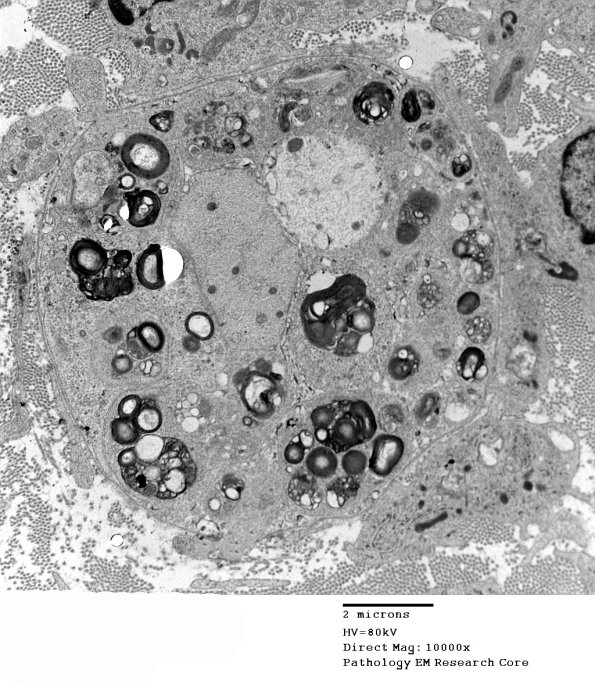

2F1A,B A denuded axon is accompanied by multiple macrophage processes containing myelin debris. (electron micrograph)